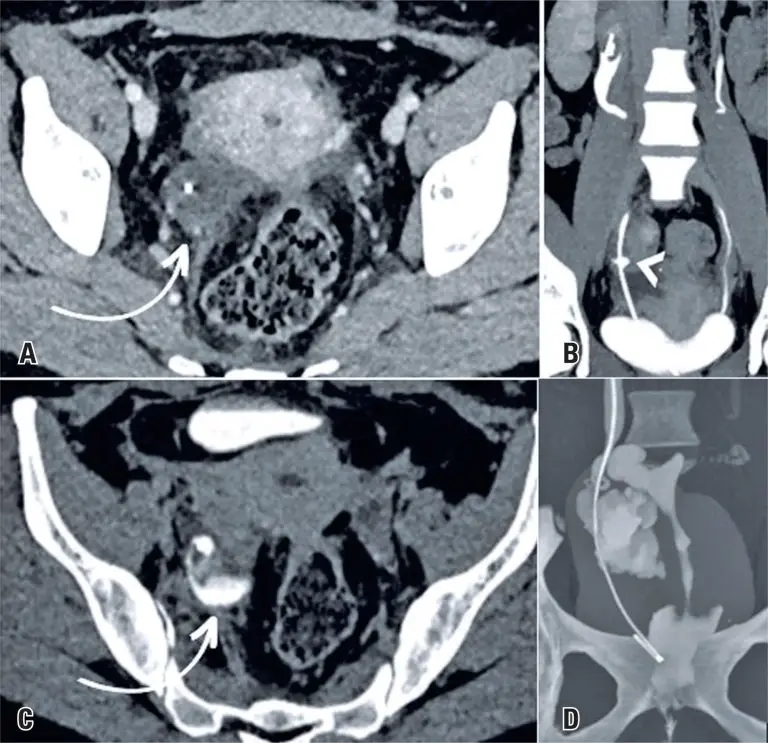

Chronic spontaneous non-aneurysmal aortic rupture treated with endovascular surgery

DOI: 10.31744/einstein_journal/2024RC1113

ABSTRACT Spontaneous non-aneurysmal aortic rupture is rare and is usually attributed to penetrating aortic ulcers, infections, tumor infiltrations, or inflammatory and collagen diseases. Chronic rupture is infrequent but extremely rare in non-aneurysmal aortas, which makes diagnosis difficult because the absence of an aneurysm can mislead the physician to rule out rupture. Here, we describe the case of an 85-year-old male, who was undergoing oncological investigation for weight loss, inappetence, and back pain. Computed tomography and magnetic resonance imaging performed 3 […]

Keywords: Aged, 80 and over; Aneurysm; Aneurysm, false; Angiography; Aorta, abdominal; Endovascular procedures; Intensive care units; Magnetic resonance imaging; Patient discharge; Penetrating atherosclerotic ulcer; Prostheses and implants; Rupture; spontaneous; Tomography, x-ray computed